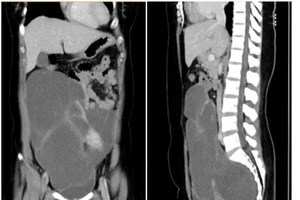

Đi tiểu nhiều, đi khám mới hay khối u 2,8 kg ở vùng chậu

18/07/2018 10:54